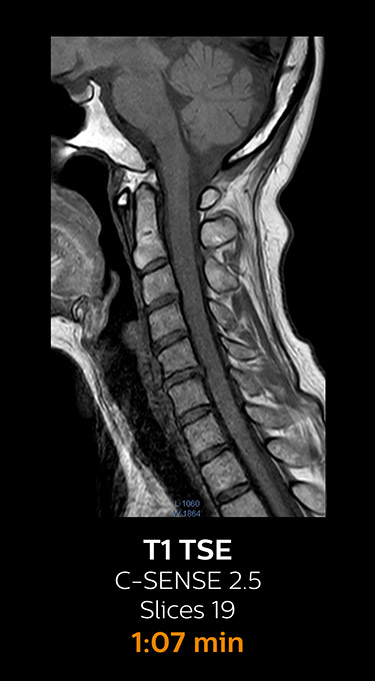

With Compressed SENSE, the scan time for the routine cervical spine examination at KNC was reduced from 13:11 to 9:52 minutes, which corresponds to 25% reduction.

MRI examination of the cervical spine with Compressed SENSE

Ingenia 3.0T CX

Scan time 9:52 min. (was 13:11 min. without Compressed SENSE)